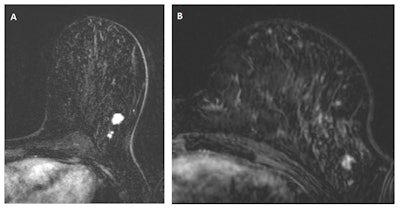

Almost one-third of breast cancers detected in a high-risk screening program using breast MRI were already visible at the last negative MRI scan, Dutch researchers have reported. The results apply to both screen-detected and interval cancers, they added.

The study team paired data from an increased-risk breast cancer screening program and the Dutch national cancer registry. Dr. Suzan Vreemann, formerly of the radiology and nuclear medicine department at Radboud University Medical Center in Nijmegen, the Netherlands, and colleagues found that 31% of cancers were visible at the initially negative MRI scan.

The study team found negative prior MRI scans for 131 breast cancers. Of these, 76 cancers were MRI-detected, 13 were mammography-detected, 16 were interval cancers, and 26 were incidental cancers. Overall, 31% of cancers were visible at the initially negative MRI scan.

"When including cancers presenting with minimal signs, 65% of the lesions were already recognizable on the prior MRI exam," the authors noted. "Both from a learning perspective and in terms of liability, it is essential that these figures are available."

These results are in line with previous studies using smaller cohorts that found 56% and 47% of breast cancers were already visible on prior MRI examinations and retrospectively assessed as BI-RADS 3 or higher. However, previous studies only included screen-detected cancers on MRI.

"To our knowledge, this study is the first to show that also 31% of interval cancers and even 35% of incidental cancers can be identified at the last negative MRI scan," Vreemann and colleagues wrote.